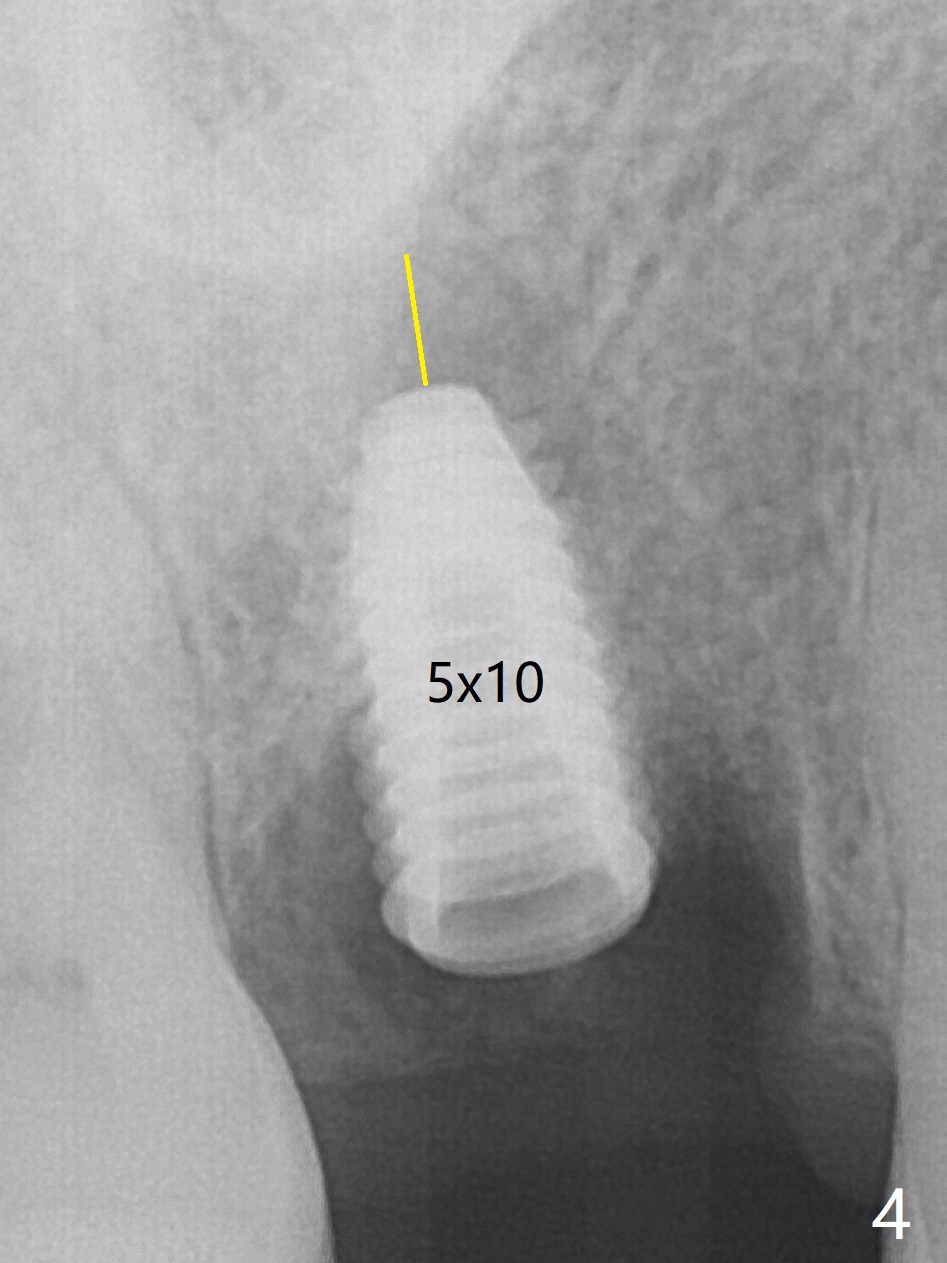

5x10

mm Immediate Implant

While the tooth #3 has a mesiodistal crack line, etiology may be due to chronic periodontitis with bruxism. After extraction, there is granulation tissue attached to the distobuccal (DB) root. The DB socket is larger than the mesiobuccal one (Fig.1). Osteotomy is initiated in the DB slope of the septum for 10 mm (Fig.2,3). Since there is ample apical bone, the depth of the osteotomy increases to 11.5 mm. When a 5x10 mm dummy implant is placed, primary stability is satisfactory (Fig.4 (yellow line: apical space)). The definitive implant remains the same dimension with deeper placement (Fig.5,6 (~ 20 Ncm)); with placement of a 6.5x4(3) mm abutment and Vanilla/Osteogen Graft (*), an immediate provisional is fabricated in place (without taking out for trimming) with sufficient clearance with the opposing dentition. It appears that the moderately long implant (10 mm) is able to achieve primary stability for immediate placement. When the provisional is removed 2 months postop, bone graft seems to be adhered to the socket (Fig.7). To improve local hygiene, the provisional does not return. The implant seems to have osteointegrated 3.5 months postop (Fig.8). The crown/abutment is loose approximately 1 year post cementation. Due to her daughter's contracting COVID 19, she postpones returning for approximately 1 year. The access hole is opened, crown/abutment (6.5x4(4) mm) removed, proximal contacts reduced, crown/abutment reseated without certainty. BW shows incomplete seating probably due to bony interference (Fig.9). A 5.5x4(4) mm can not be seated (bouncing, probably due to soft tissue interference). When a 4.5x5(4) mm abutment (UF) is seated, hand tightening is smooth, confirmed by BW (Fig.10). Two weeks later, the new crown is cemented intraorally. The crown/abutment is removed for cleaning. The abutment screw is torqued at 20 NCM.